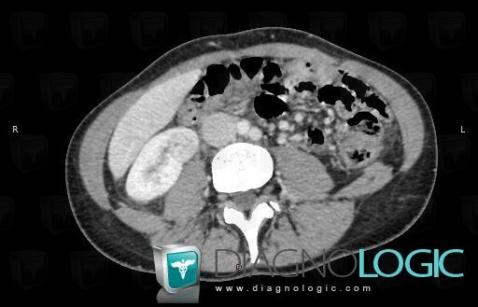

Abscess, Kidney, CT

Here is the specific information in the key image above:

- Diagnosis Abscess, Location(s) Kidney, with gamuts Complex / Multiloculated renal mass